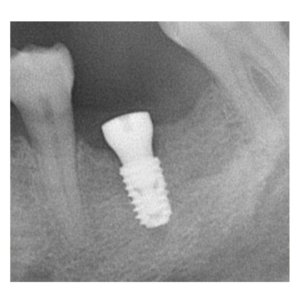

治療途中のインプラント症例

治療途中のインプラント症例です。